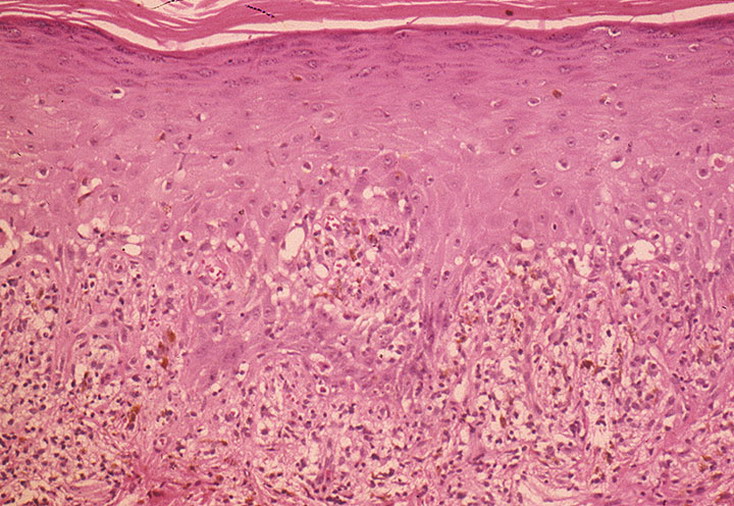

Фото Красного Плоского 103 фото